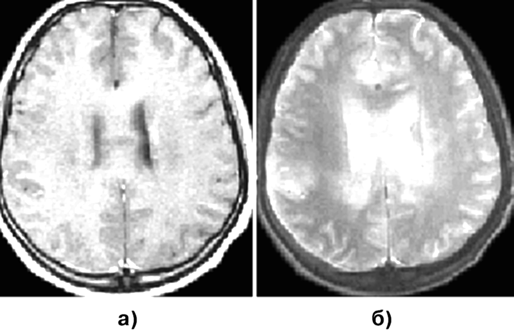

Наиболее общим проявлением ЦГ является наличие на КТ диффузно инфильтративного поражения, распространяющегося по белому веществу мозга, без усиления после внутривенного введения контрастного вещества и без деструкции мозгового вещества.

МРТ более информативна: выявляется обширное поражение паренхимы, особенно белого вещества, в виде областей повышения сигнала на Т2-взвешенных томограммах без четких контуров, переходящих в сигнал, присущий непораженному мозгу. Смещение борозд и желудочковой системы может быть слабо выражено (рис. 10б). На Т1-взвешенных изображениях теряется обычная разность в сигналах между белым и серым веществом мозга, извилины утолщены, субарахноидальные щели сдавлены (рис. 10а). Диффузная природа поражения при ЦГ приводит к тому, что его надо дифференцировать с демиелинизирующими заболеваниями. Поэтому для подтверждения диагноза необходима биопсия наиболее измененных (по данным МРТ) участков мозга. В далеко зашедшей стадии болезни могут появляться отдельные участки накопления контраста. Лептоменингиальный глиоматоз может быть похож на менингиальный карциноматоз.

Рисунок 10. Глиоматоз головного мозга: МРТ с контрастным усилением:

а — Т1-взвешенные изображения; б — Т2-взвешенные изображения